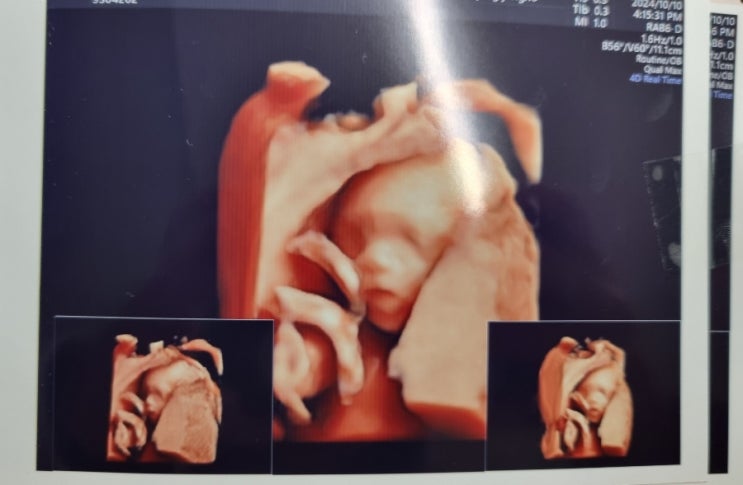

둘째 임신 30주 그간의 이야기

둘째 임신은 임신이 되는 시작부터, 중기까지 이벤트가 참 많았다. 중기 이후로는 첫째 돌봄에 바빠서 주수...